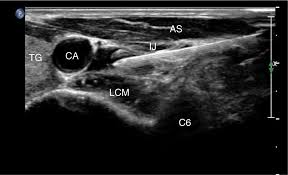

Τεχνική αποκλεισμού του γαγγλίου καθοδηγούμενη από υπέρηχο και χρήση έγχρωμου Doppler ροής

Ο ασθενής βρίσκεται σε ύπτια θέση με τον αυχένα ελαφρώς τεντωμένο και το κεφάλι γυρισμένο προς την αντίθετη πλευρά. Αναγνωρίζεται το φύμα του Chassaignac στην εγκάρσια απόφυση του Α6 σπονδύλου και οι επιμήκεις τραχηλικοί μύες άνωθεν αυτού. Η έγχυση γίνεται στην περιτονία αυτών των μυών. Εγχύεται τοπικό αναισθητικό και κορτιζόνη. Το γάγγλιο μπορεί στην πορεία να απονευρωθεί με χρήση ραδιοσυχνοτήτων και ή κρυοπηξίας για μακρό σε διάρκεια θεραπευτικό αποτέλεσμα.